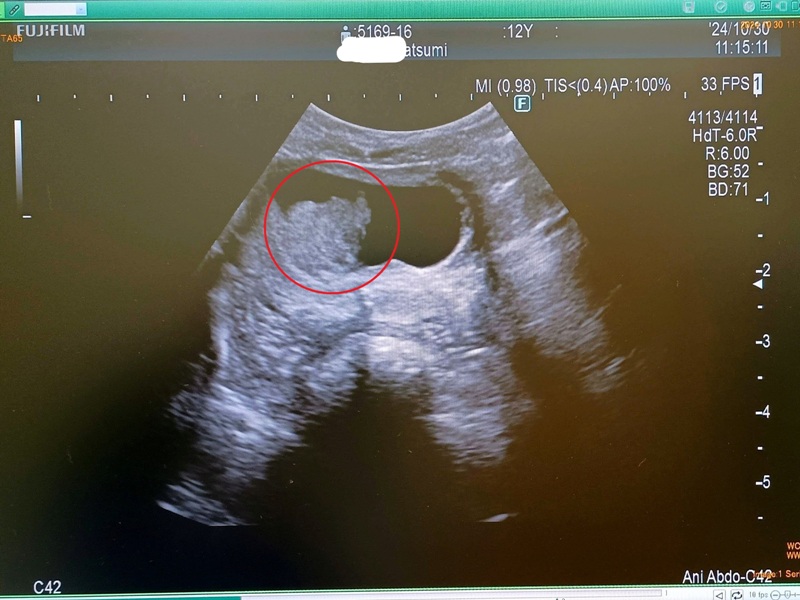

処方された薬を2週間服用し、10月30日に2回めの通院。この日、再び膀胱の超音波検査を受けました。

今回は安静状態で連れてくることができたためか、腫瘤部分の輪郭がはっきりと確認できました。膀胱の内腔に向かって、表面に凹凸のある塊が突き出している様子がわかります。

確定診断にはカテーテルで組織を採取して病理検査を行うのが一般的だそうですが、採取がスムーズにいかない可能性もあり、先生もその必要性を慎重に検討されていました。

結論として、身体に診断のための負担をかけることは避け、これまでの検査結果や投薬への反応などから総合的に判断して、膀胱の「移行上皮がん(尿路上皮がん)」として治療を進めることになりました。